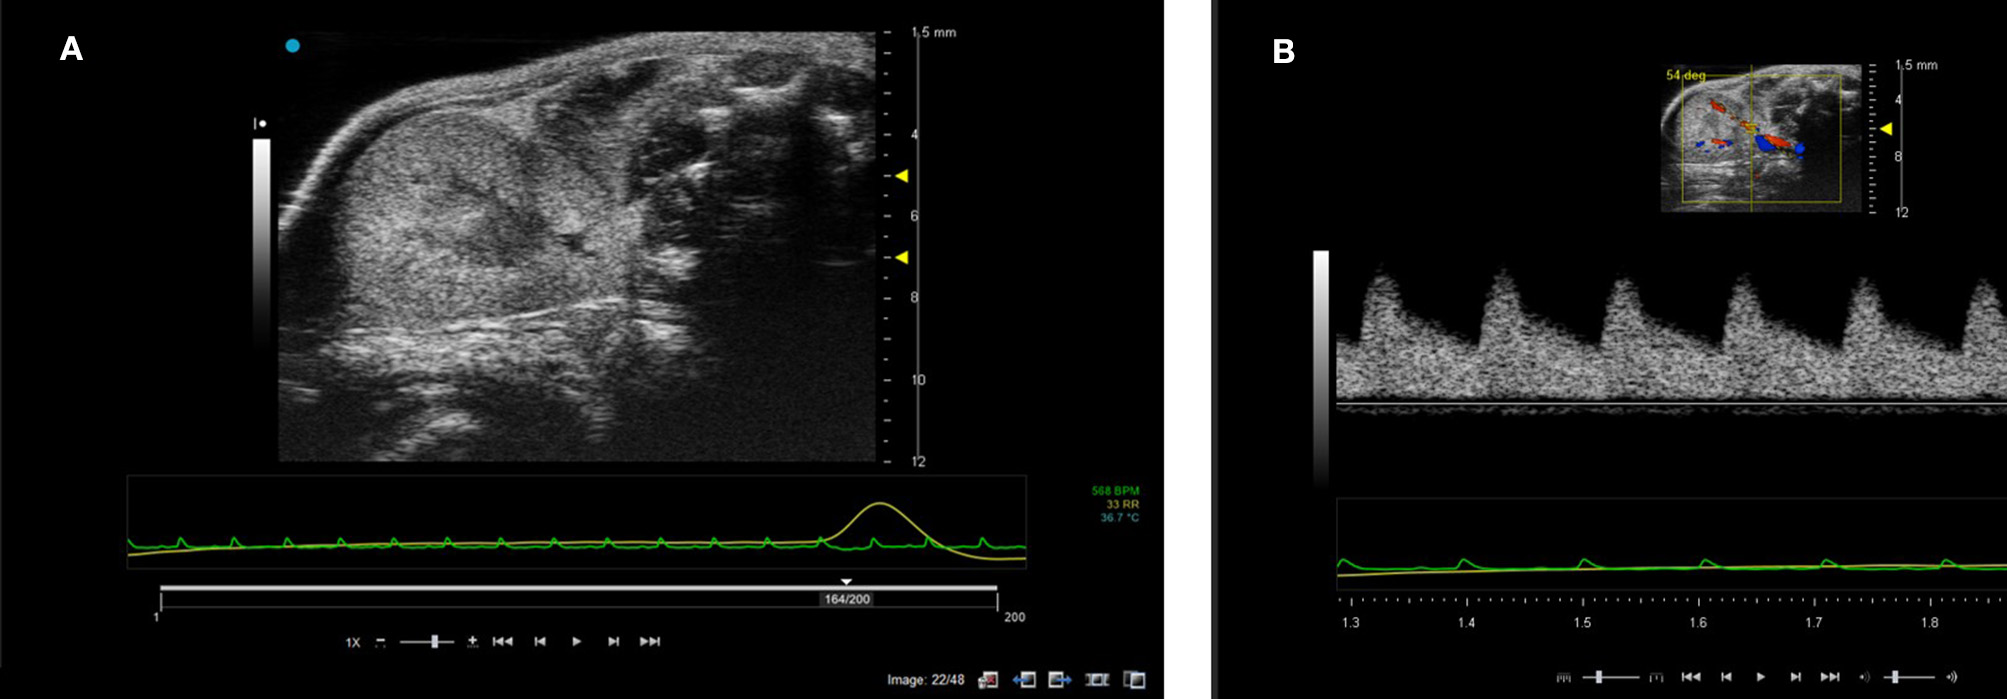

Preclinical Ultrasound—Kidney Applications

The kidneys in a mouse can either be scanned with the mouse in supine or prone position. The hair can be removed firstly with electric hair clippers and then with depilatory cream. Unless contrast agents are being used, high temporal resolution is not required for imaging the kidneys so multiple focal positions can be selected across the depth of the kidney. Frequencies used tend be between 30 and 40 MHz dependent on the size of the animal. B-mode imaging is used to locate the kidney with the cortex of the kidney tending to have increased backscatter (brighter) compared to the central medulla. Both kidneys can be scanned in the adult rodent. Figure 14 shows an image of a mouse kidney and a duplex image using color Doppler to locate the vessel and direction of flow before placing the spectral Doppler sample volume within the vessel. Renal blood flow can be measured and the renal arterial resistive index calculated (peak systolic velocity—the end diastolic velocity) /peak systolic velocity) and its value indicative of the resistance to blood flow in the vascular bed [19].

FIGURE 14

www.frontiersin.org

Figure 14. (A) B-mode image of kidney. Note the two focal positions on the image. (B) Duplex image of mouse kidney. In the Duplex image, the sample volume is localized using the color Doppler box as an indicator to show where the vessel lies and direction of blood flow.